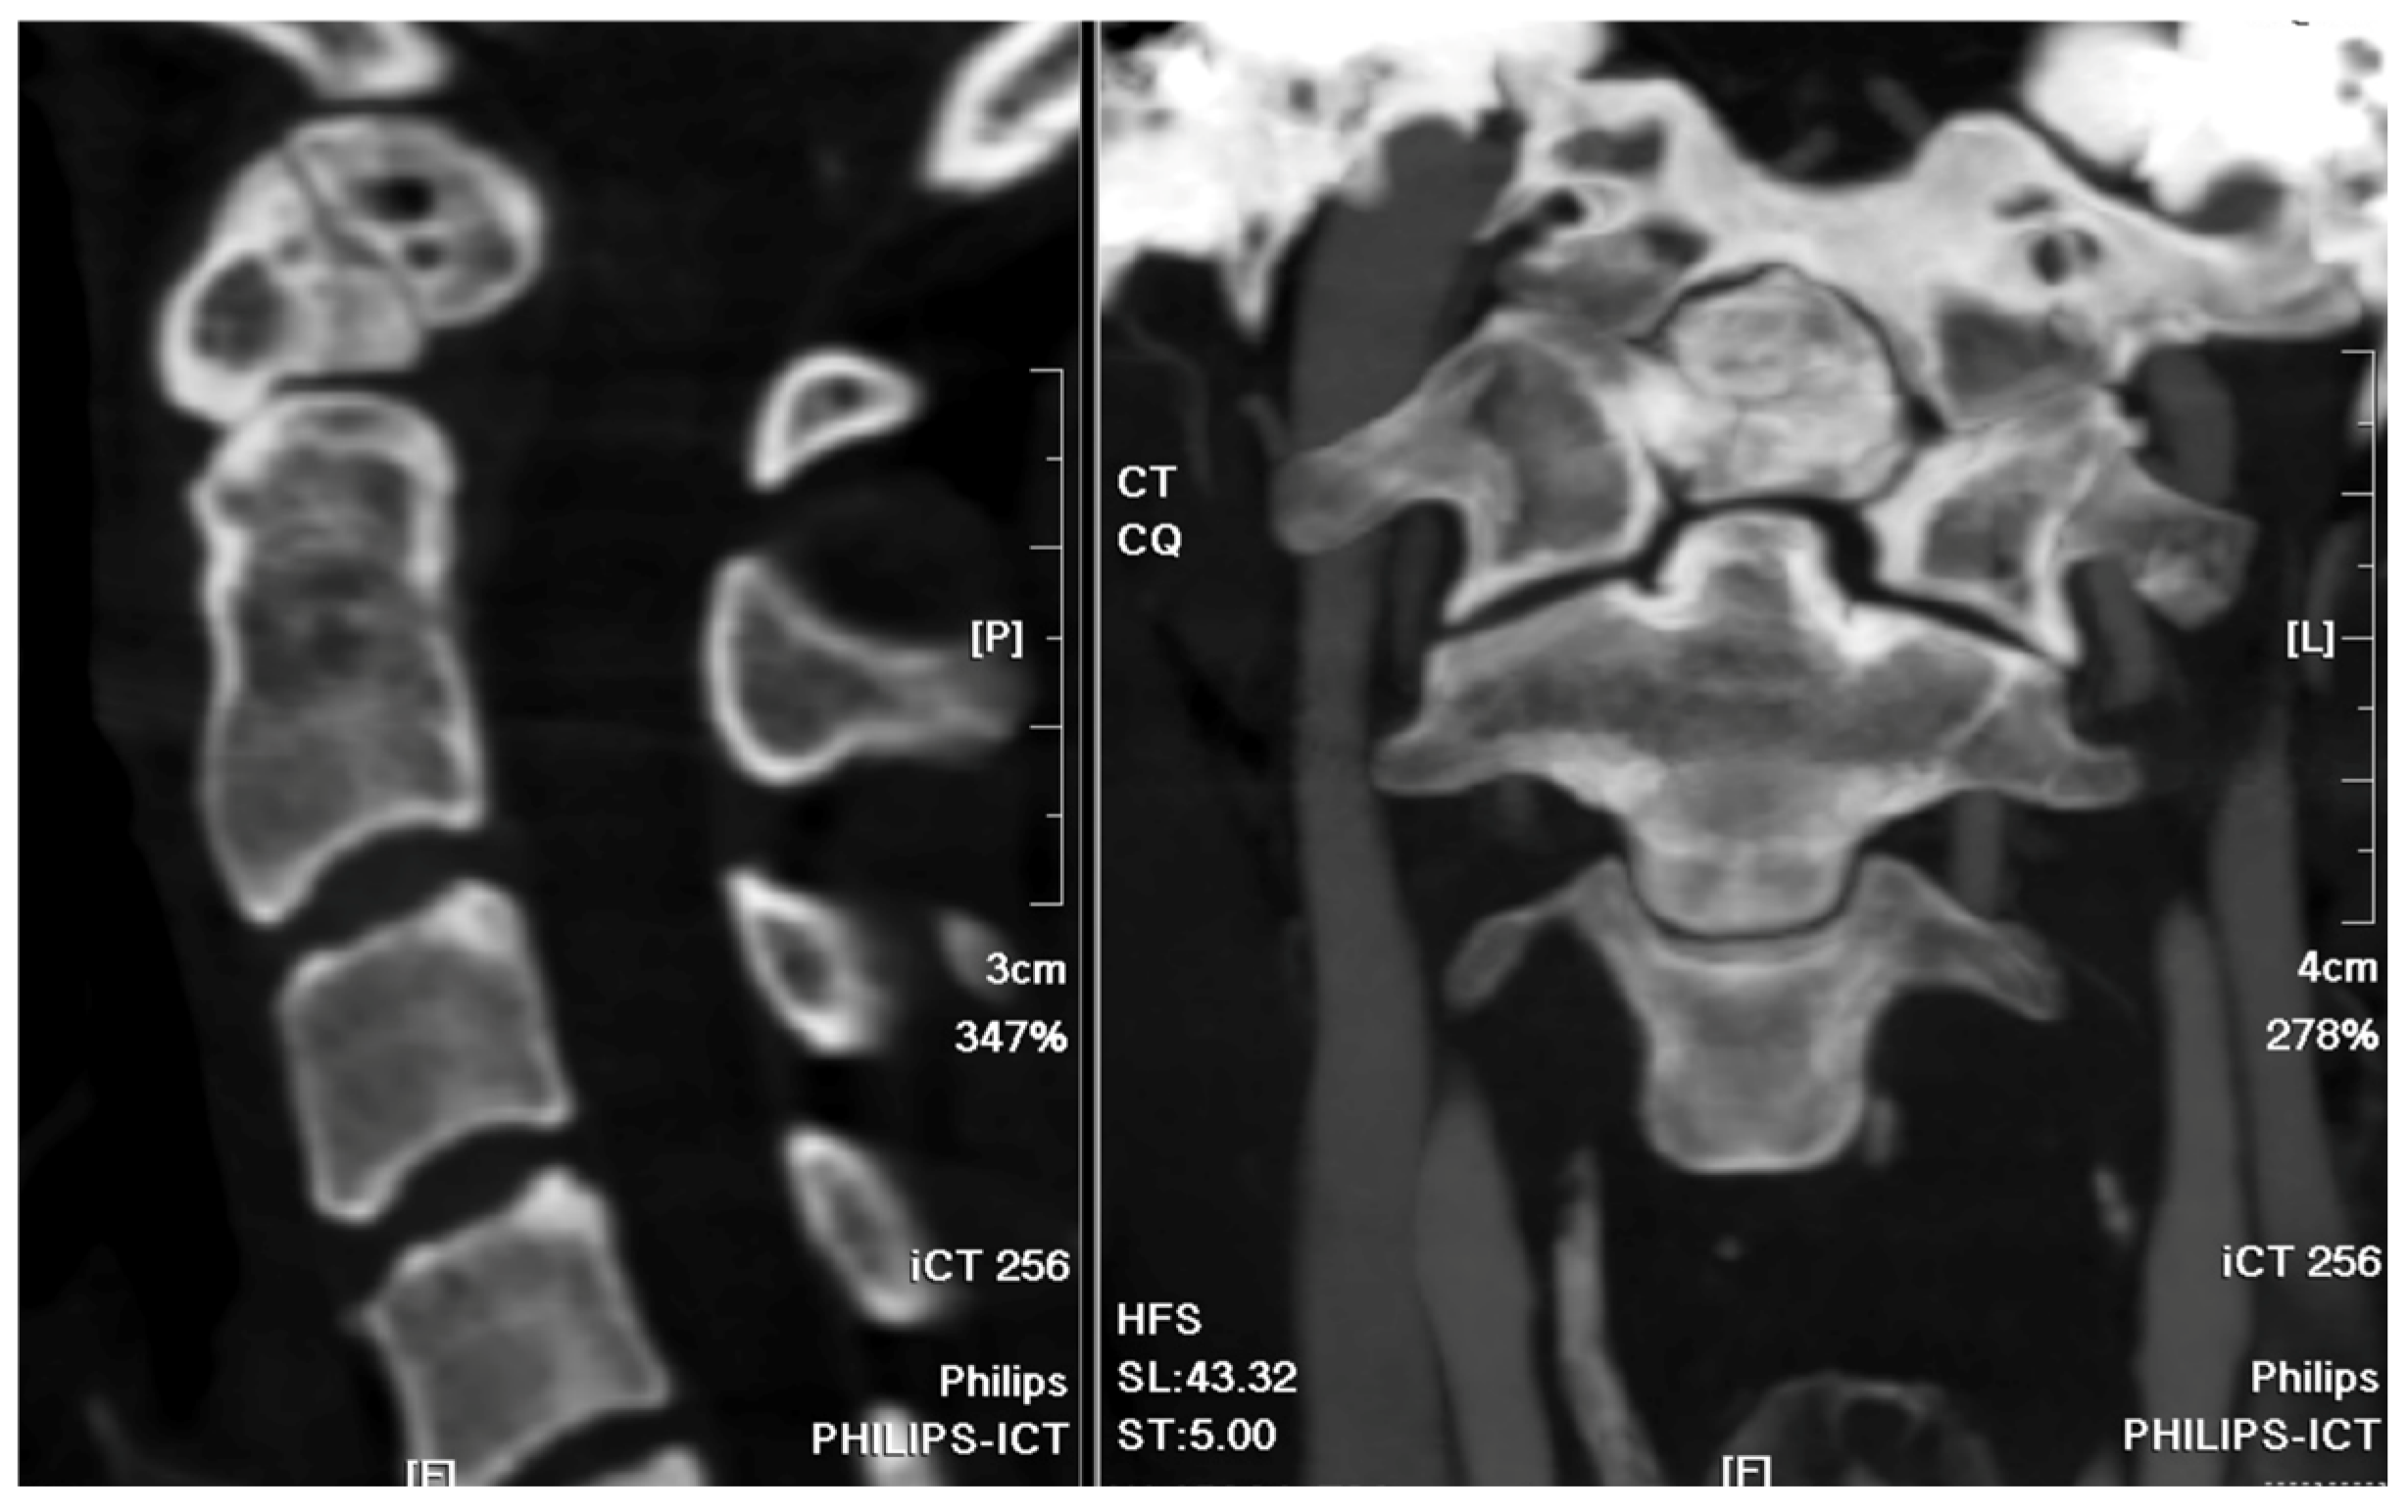

A 37-year-old female with no prior medical history or spinal surgeries presented to our neurosurgery outpatient department five months after a motorcycle traffic accident. Initially diagnosed with a C2 fracture at a local emergency department, she received only conservative treatment and wore a neck collar. Subsequent to the accident, she experienced persistent neck pain radiating to both shoulders and upper back, right-hand numbness with associated weakness, headaches, neck stiffness, and an unsteady gait. An initial cervical spine X-ray revealed the asymmetric widening of the distance between the right C1 arch and the dens with suspected atlantoaxial subluxation (Figure 1). Computed tomography revealed non-fused bony elements (Figure 2). Further cervical spine magnetic resonance imaging (MRI) (Figure 3) highlighted os odontoideum with C1-C2 subluxation and slight spinal cord atrophy at the C1-C2 level due to instability. There was also evidence of ventral compression at the C1-C2 level from chronic inflammatory pannus and granulation tissue.

Figure 1. Cervical spine X-ray images. (a) Open mouth view revealed the asymmetric widening of the distance between the right C1 arch and the dens with suspected atlantoaxial subluxation. (b,c) Flexion and extension also showed suspected atlantoaxial subluxation.